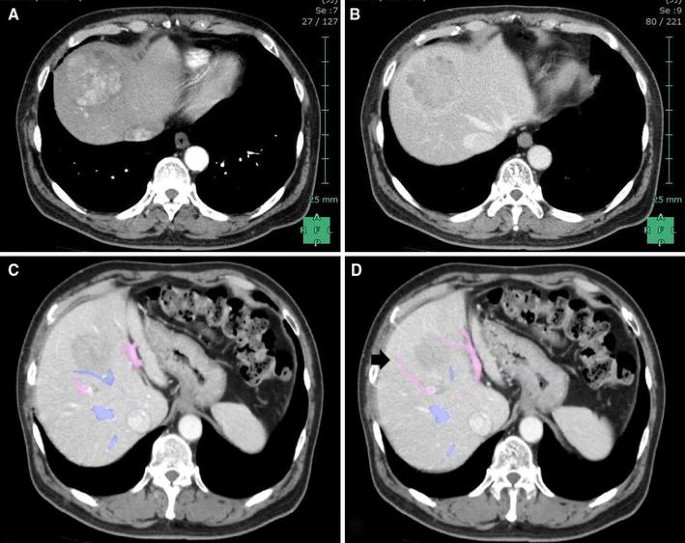

A 68-year-old man with a history of diabetes mellitus and hypertension, but without hepatitis B or C virus infection, was sonographically confirmed to have a large hepatic tumor during follow-up. He had undergone exploratory laparotomy for colon diverticulitis 7 years prior. Abdominal computed tomography revealed a 6.5-cm liver mass, which showed typical HCC features of early arterial enhancement and portal venous washout, located at hepatic segments 4, 5, and 8 and compressing the middle hepatic vein (MHV, Fig. 1A–C). The tumor was supplied by the ventral branches of the right anterior Glissonian pedicle (Fig. 1D). Preoperative evaluation of the liver reserve revealed Child–Pugh class A liver cirrhosis and the 15-min retention rate of indocyanine green (ICG15) was 14 %. The serum levels of tumor markers for alpha-fetoprotein and protein induced by vitamin K absence or antagonist-II were 2.6 ng/ml and 132 mAU/ml, respectively. Preoperative surgical planning using the three-dimensional volume analyzer Synapse Vincent™ (FUJIFILM Co., Japan) suggested the feasibility of limited anatomic subsegmental resection (Fig. 2) instead of central bisegmentectomy (which consisted of 493-ml volume, 46.2 % total liver volume) according to Makuuchi’s criteria [11].

Enhanced abdominal computed tomographic image showing A early arterial phase of HCC centrally located in the liver and B, C compression of the MHV. D Ventral branch of the right anterior portal trunk is pointed to by the arrow. Pink portal vein, blue hepatic vein (Color figure online)